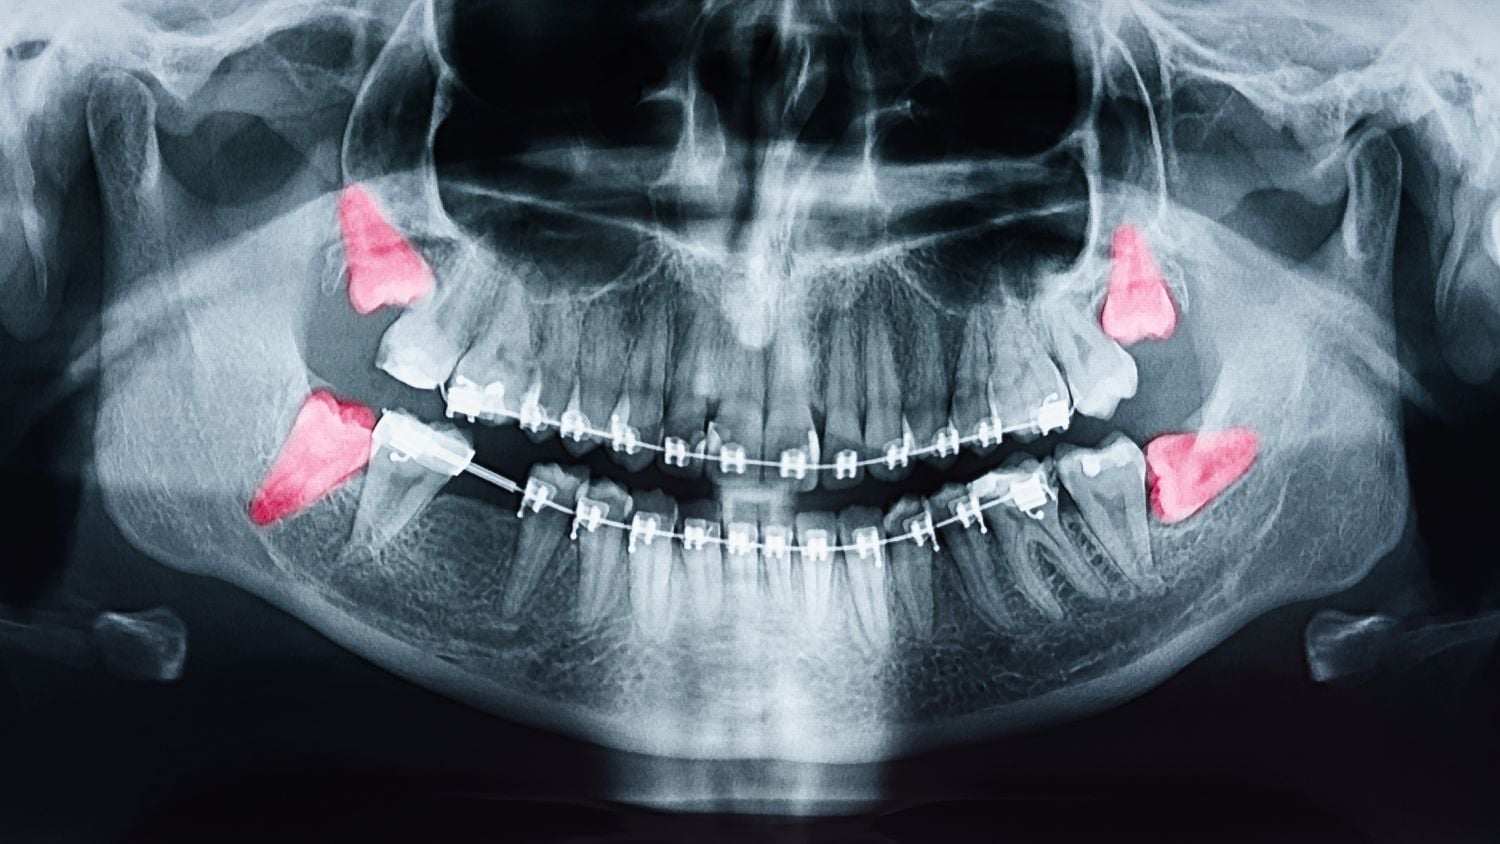

Röntgenaufnahmen zeigen die genaue Lagebeziehung zu Nervenstrukturen. Besonders im Unterkiefer verläuft der Nervus alveolaris inferior in unmittelbarer Nähe. Eine präzise Planung reduziert das Risiko sensibler Störungen.

Panoramaschichtaufnahmen geben einen Überblick über Lage und Stellung der Zähne. Bei komplexer Anatomie kann eine dreidimensionale Bildgebung sinnvoll sein. Diese zeigt den Verlauf wichtiger Nervenstrukturen.

Die Entscheidung zur Entfernung basiert auf Symptomen, radiologischen Befunden und individueller Risikobewertung. Asymptomatische Zähne werden differenziert beurteilt.